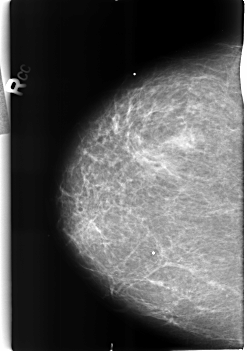

B_3217_1.RIGHT_CC

RIGHT_CC LINES 4560 PIXELS_PER_LINE 3200 BITS_PER_PIXEL 12 RESOLUTION 50 NON_OVERLAY